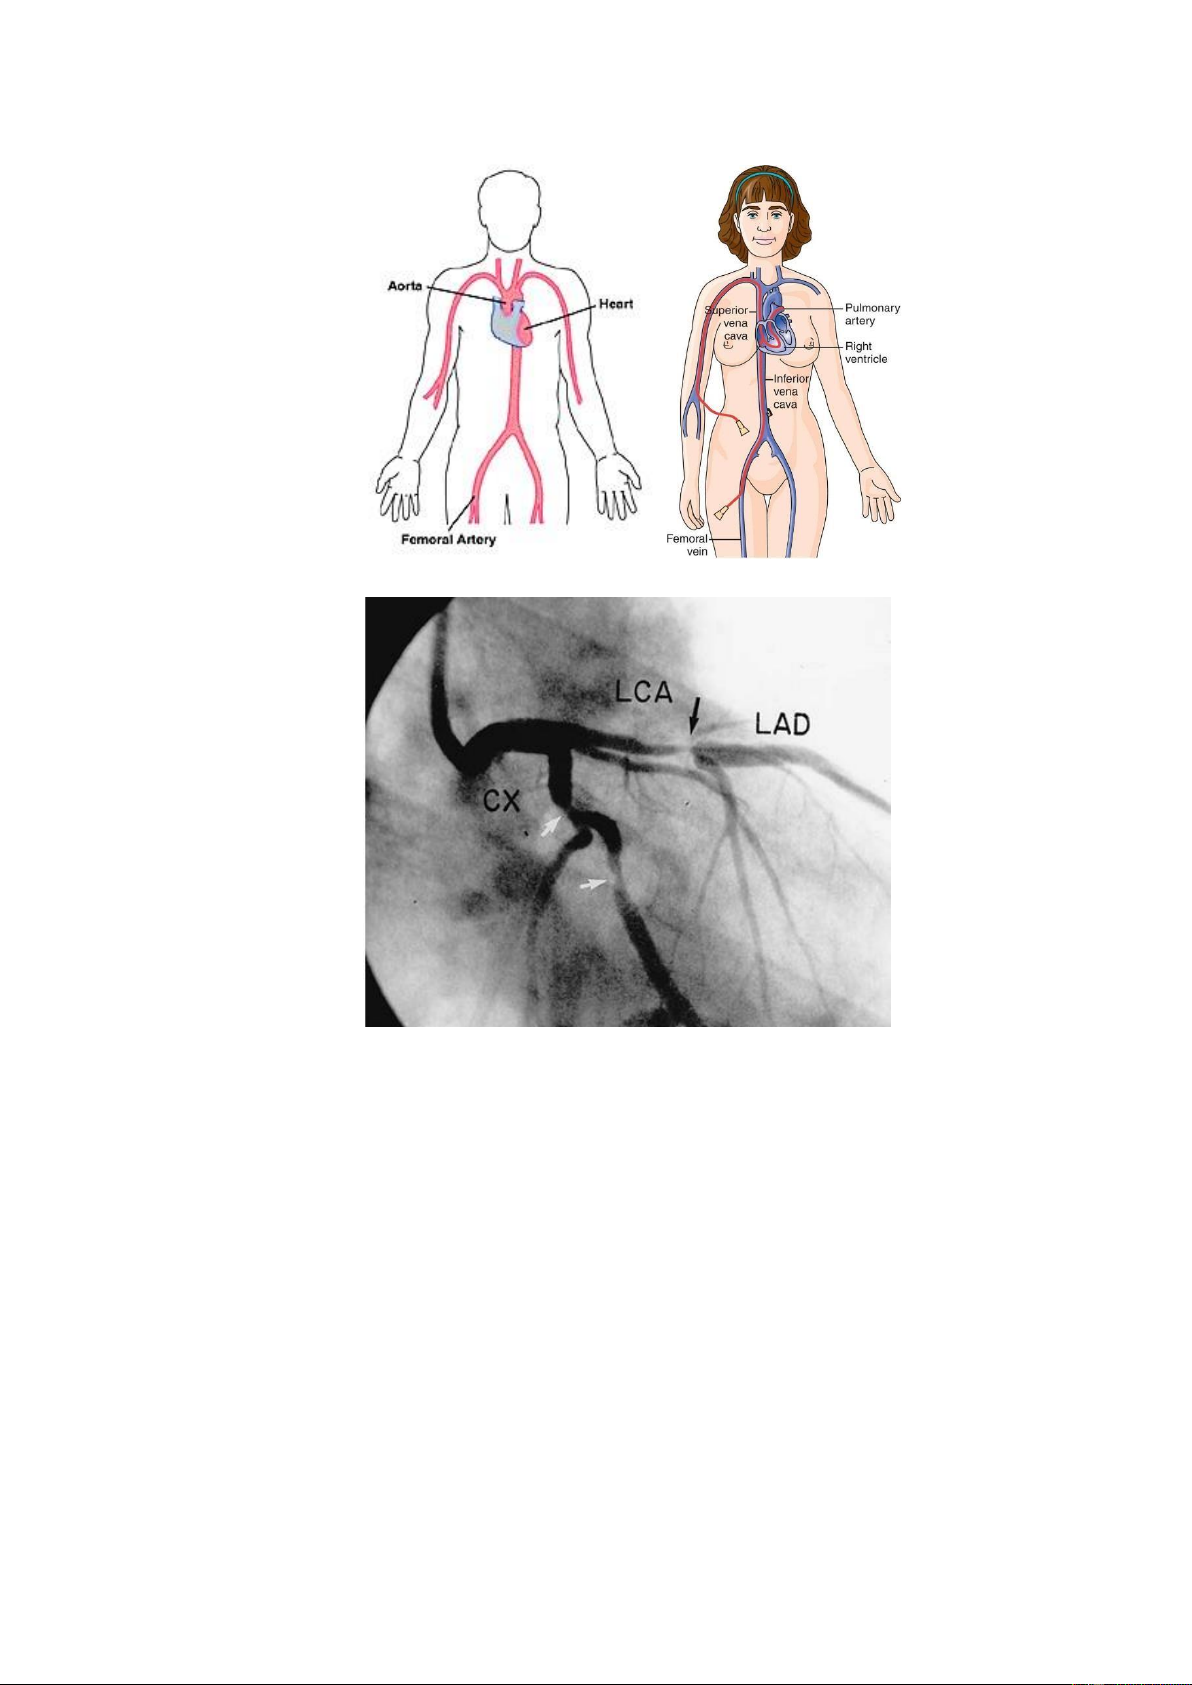

1.2.5. Chụp động mạch v nh •

Chụp động mạch v nh kh ng x m lấn: Chụp động mạch v nh kh ng x m lấn

với CT Scan nhiều lÆt cắt (MSCT, 64 lÆt cắt) cho phØp dựng h nh v cho phØp

chẩn đoán khá chính xác mức độ tổn thương hẹp cũng như calci hóa động mạch v nh. •

Chụp động mạch v nh x m lấn: Thăm dò xâm lấn chẩn đoán chính xác có

hẹp động mạch v nh, về mức độ v vị tr hẹp của từng nhÆnh động mạch v nh. lOMoAR cPSD| 39651089

H nh 15. Th ng tim trÆi (BŒn trÆi) v th ng tim phải (BŒn phải)

H nh 16. Chụp động mạch v nh với hẹp nặng nhÆnh gần của động mạch liŒn thất

trước v hẹp vừa nhánh mũ. 1.2.6. XØt nghiệm